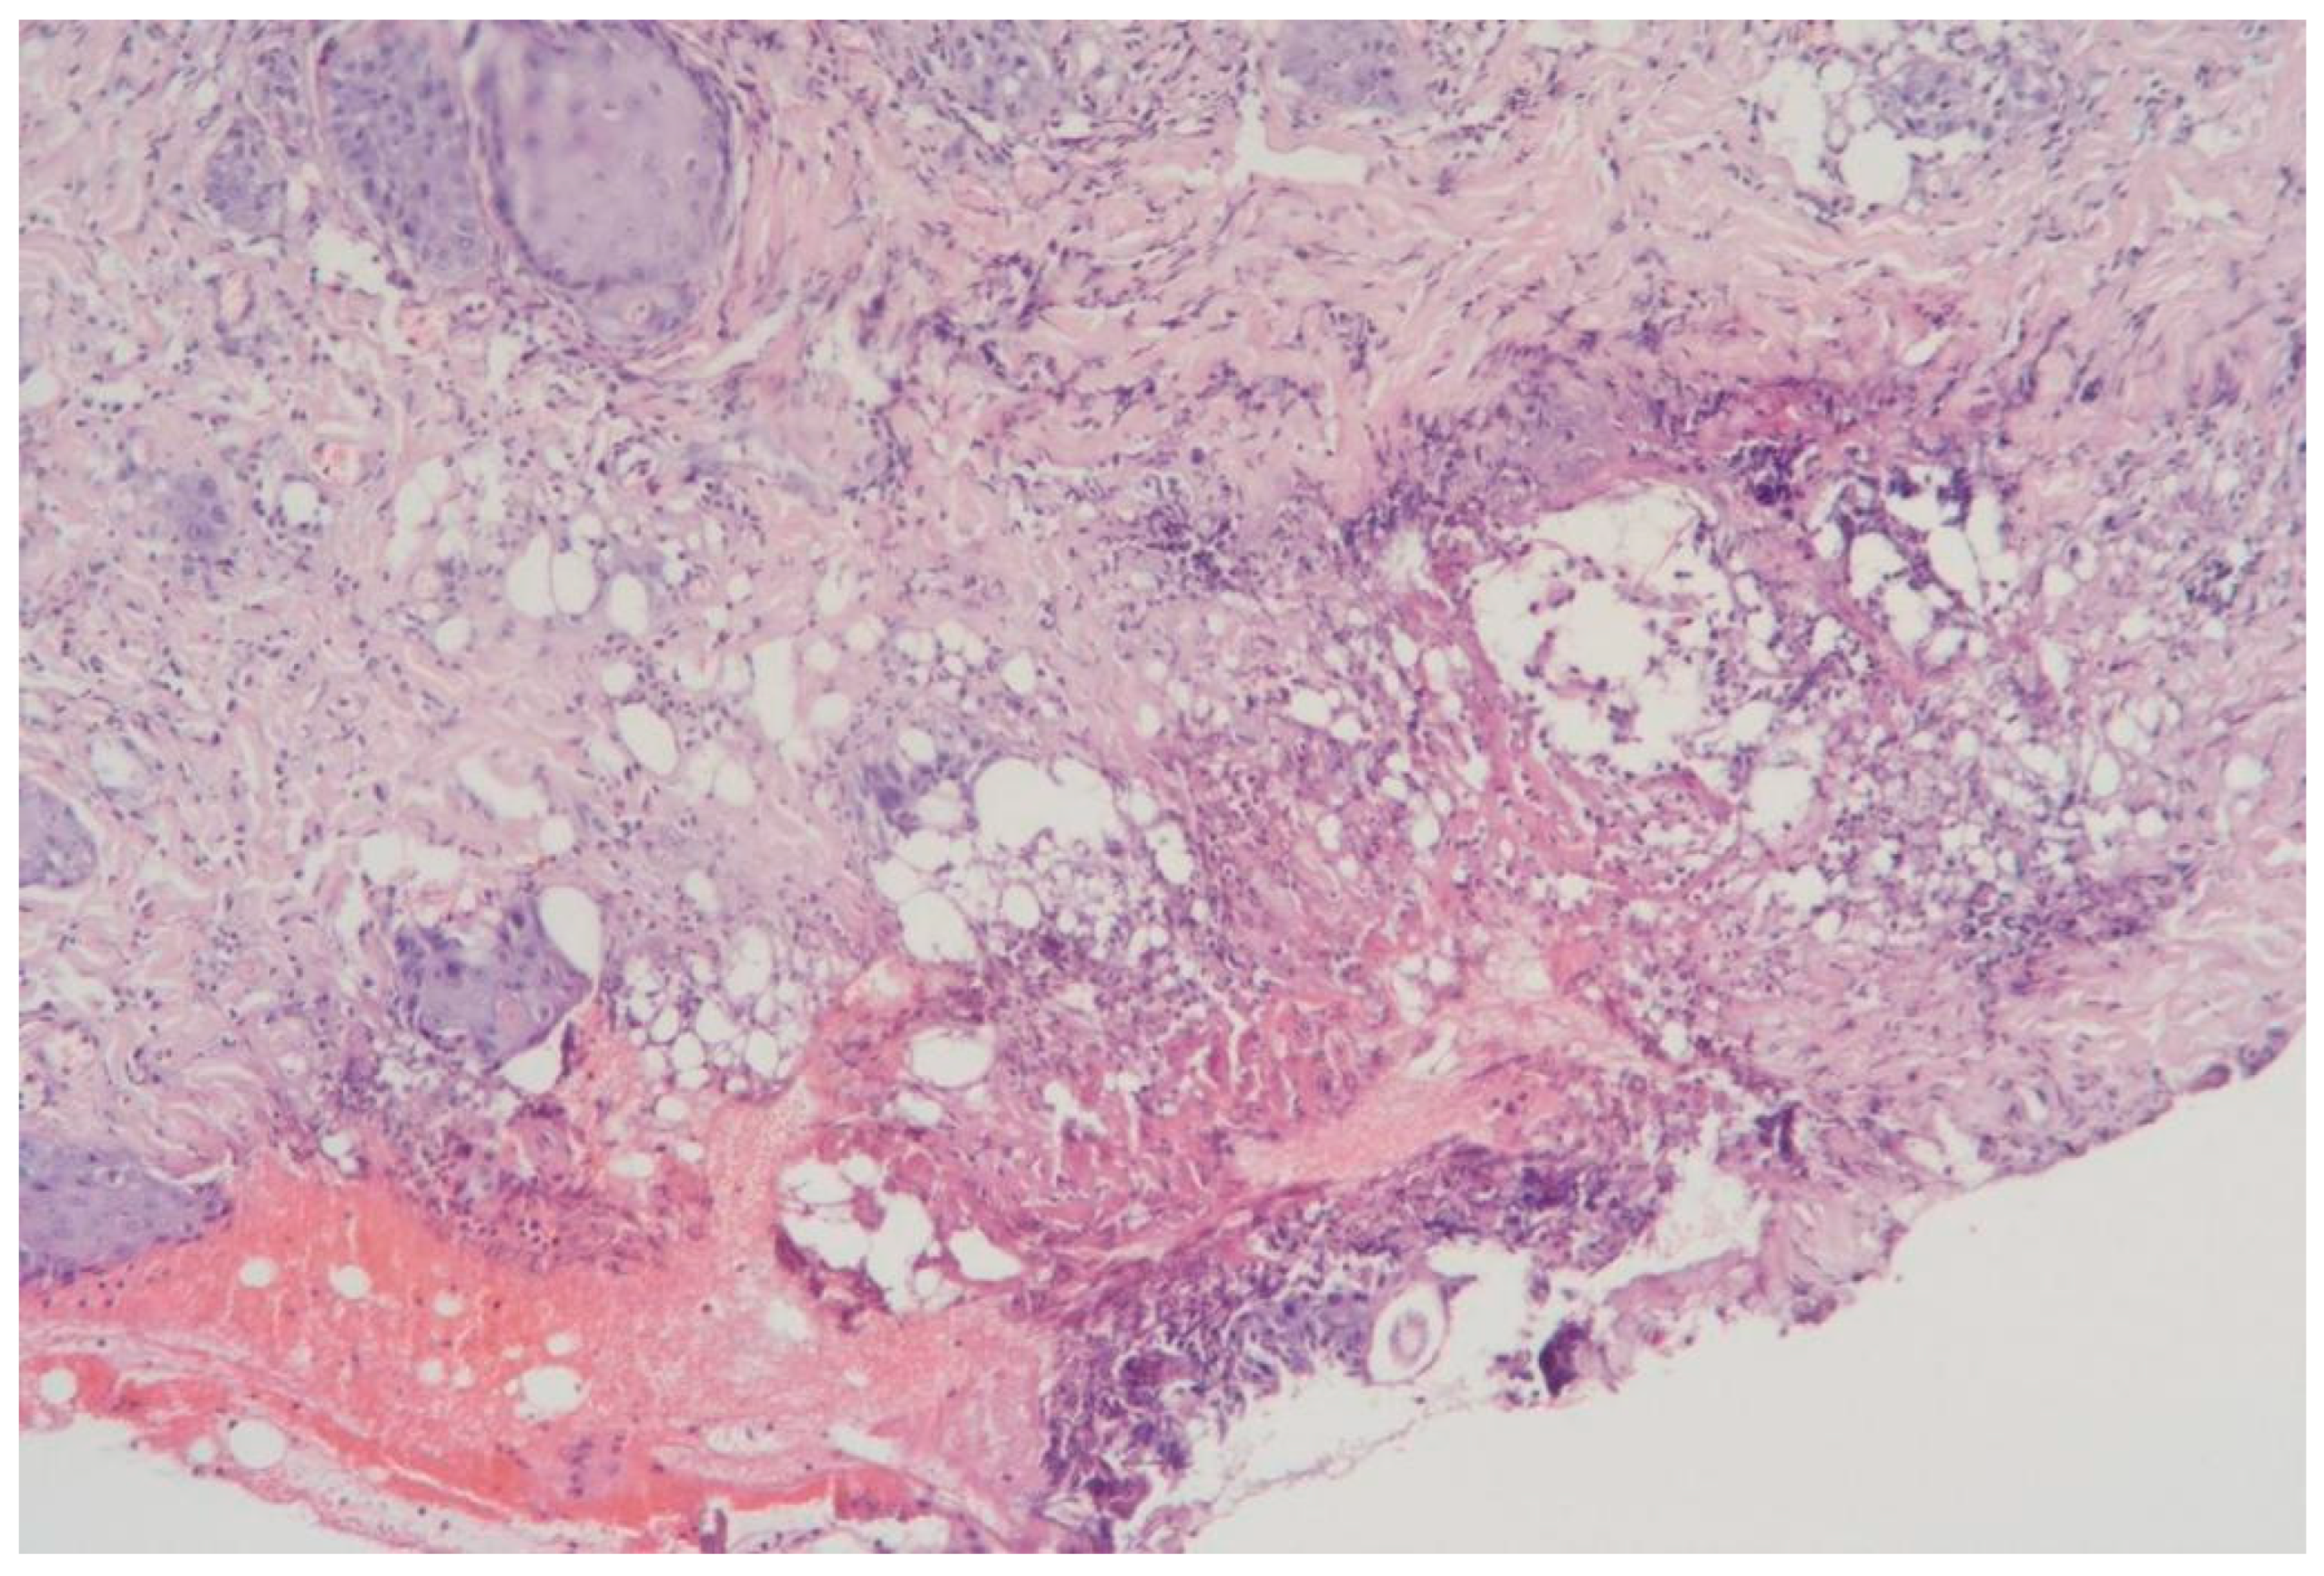

3.1.7. Clinical Case 7: Adipose Tissue Dissection Area, Scalpel Incision (See Figure 8)

Description: The structure of the subcutaneous adipose tissue was preserved, with the vessels being dilated and congested.

Figure 8.

Changes in subcutaneous adipose tissue following scalpel incision. H&E staining, 10× objective magnification.